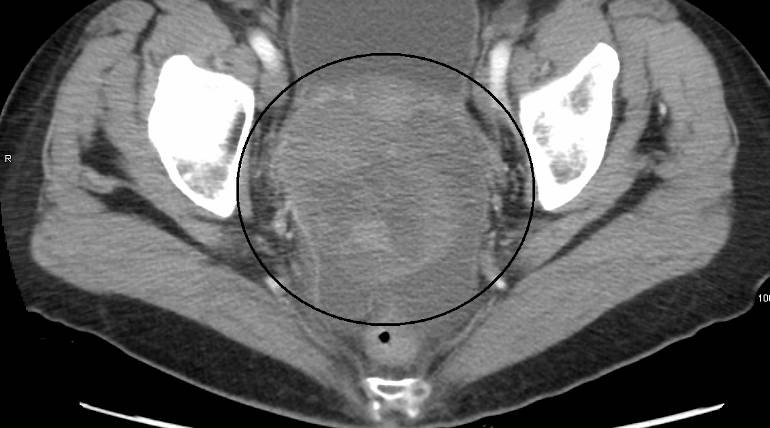

Cytoreduction surgery (secondary surgery) for ovarian cancer patients failed the study, New England Journal of Medicine.

The Gynecologic Oncology Group (GOG)-0213 (NCT00565851) published a study data from ovarian cancer patients trial in the New England Journal of Medicine. The study trial states that secondary surgery (cytoreduction) followed by chemotherapy for ovarian cancer patients shown zero improvements in the survival rate compared to the survival rate of ovarian cancer patients undergone chemotherapy alone.

Researchers undergoing trial for nearly 48.1 months of study on ovarian cancer patients, the secondary surgery followed by chemotherapy women survived only 50.6 months compared to the ovarian patients whose overall survival rate prolongs for 64.7 months for chemotherapy treatment alone. The worldwide clinical trial included patients with epithelial ovarian, primary peritoneal, or Fallopian-tube cancer.